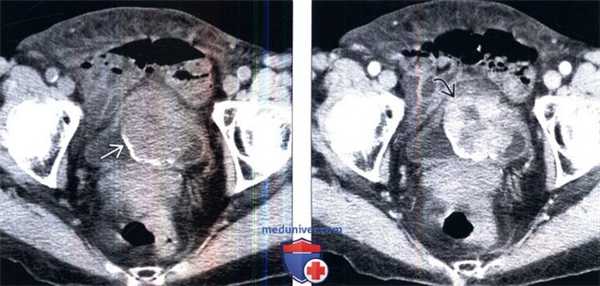

(Слева) КТ без контрастирования, аксиальный срез: у женщины 76 лет с макрогематурией и болью в малом тазу определяется крупное образование мочевого пузыря с частично кальцинированной поверхностью.

(Справа) КТ с контрастированием, аксиальный срез: у этого же пациента определяется прерывистое контрастирование объемною образования. Околопузырная жировая клетчатка, прилегающая к образованию, не имеет четких границ, что позволяет предположить пристеночное распространение этого процесса. (Слева) КТ с контрастированием, более каудальный аксиальный срез: у этого же пациента определяется прерывистое контрастирование объемного образования с зоной центрального некроза.

(Справа) КТ с контрастированием, аксиальный срез: у этого же пациента определяется прерывистое контрастирование объемною образования. Околопузырная жировая клетчатка, прилегающая к образованию, не имеет четких границ, что позволяет предположить пристеночное распространение этого процесса.